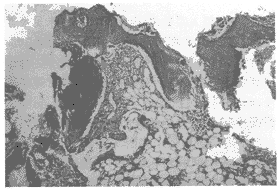

所有动物伤口I期愈合,无感染和窦道形成。肌肉内植入实验组织学观察3周时未见炎性细胞聚集及肌肉坏死,12周材料开始降解,36周时材料植入区部分被网状结缔组织和少许纤维肉芽组织修复,有少许中性粒细胞和巨噬细胞浸润,未见多核巨细胞。骨内长期植入实验X线摄片见6周时骨折愈合,无畸形(图1)。材料在12周前可清晰显影。组织学观察3周时骨折端有明显骨痂生成,材料在髁部与骨组织直接接触,在髓腔中材料周围有明显新骨生成,无中性粒细胞、淋巴细胞聚集,偶见巨噬细胞(图2)。6周时骨折均愈合,炎性细胞减少。36周时材料在进一步降解和被新骨和纤维组织修复中,可见活跃的成骨细胞和少许中性粒细胞、巨噬细胞和多核巨细胞(图3)。各组动物胸腺和脾脏组织学检查未见异常反应,淋巴胞增殖中心无增殖反应。SEM观察见材料植入前表面仅少许HA分布,植入后材料表面早期即有HA结晶沉积,6周时最多,分布均匀(图4),12周时HA有所减少。

图3 术后36周,材料部分降解和被新骨、纤维组织修复。HE ×40

Fig 3 The implant was partially degraded and replaced by new bone and connective tissue.HE ×40